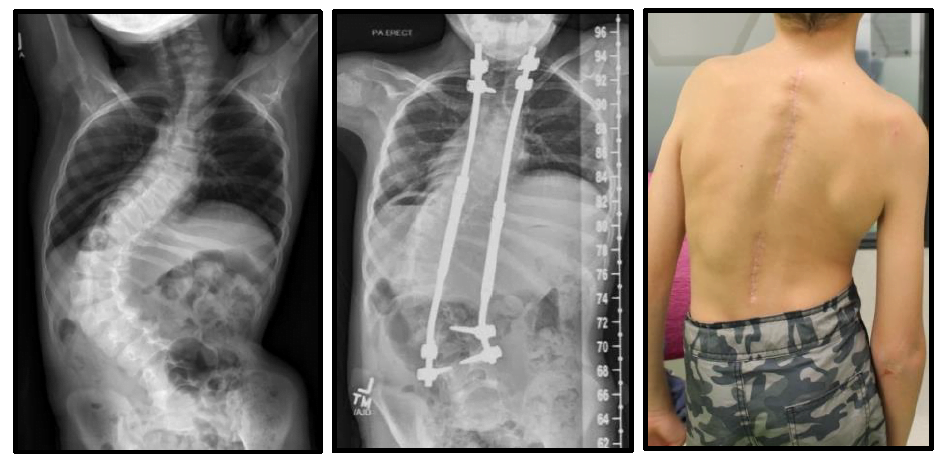

This surgery is required for younger patients who have a moderately severe scoliosis or complex spinal deformity which continues to worsen and is not treatable by bracing. It usually involves both the thoracic and lumbar spine.

While asleep facedown, two short incisions are made at either end of where the growing rods are to be placed. Usually two custom made titanium rods with special screws and hooks are attached carefully to the spine at each end. The aim is for your child's spine to continue to grow while the rods are in place. Spinal cord monitoring is used to keep a check on the impulses from the brain to the limbs to ensure the spinal cord is functioning normally during surgery. The surgery is a 'minimally invasive' procedure and as such any blood loss is expected to be minimal and the time in theatre under anaesthetic is approximately 3 - 4 hours.

The goal of this surgery is to prevent the scoliosis or kyphosis from continuing to get worse while the spine is allowed to grow, and to gain some correction as best as possible. The titanium rods have the special ability of being able to be lengthened regularly (approximately every six months) as your child grows. These lengthening procedures are performed mostly as a day procedure and very occasionally may require an overnight stay. It is expected that the lengthening procedures should not disrupt your child to any great extent. There is usually no need for a brace to be worn while you child has growing rods.

Your surgeon will advise when it is time for a permanent surgical solution, once your child has grown sufficiently. At this time the growing rods will be removed and a final correction with different rods and fusion will be performed.